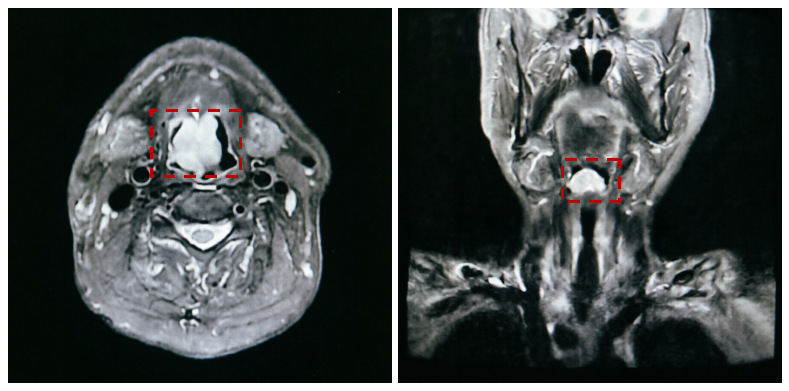

68岁的张大爷(化名)因“咯血1月余”于3月来到我院耳鼻咽喉-头颈外科就诊。经检查,张大爷确诊为喉鳞状细胞癌。然而,喉部这颗肿瘤仅仅是危险的冰山一角。

刘吉峰主任医师介绍,除了喉癌,患者还合并有终末期尿毒症(慢性肾脏病5期)、极高危高血压等多种严重基础疾病,日常只能靠规律透析维持生命。追溯其病史,患者有着长达30年的高血压史,曾发生过脑出血,还因肾癌做过手术。此次入院时,张大爷的血压一度飙至210/125mmHg,且波动剧烈,伴有呼吸困难及心衰症状。